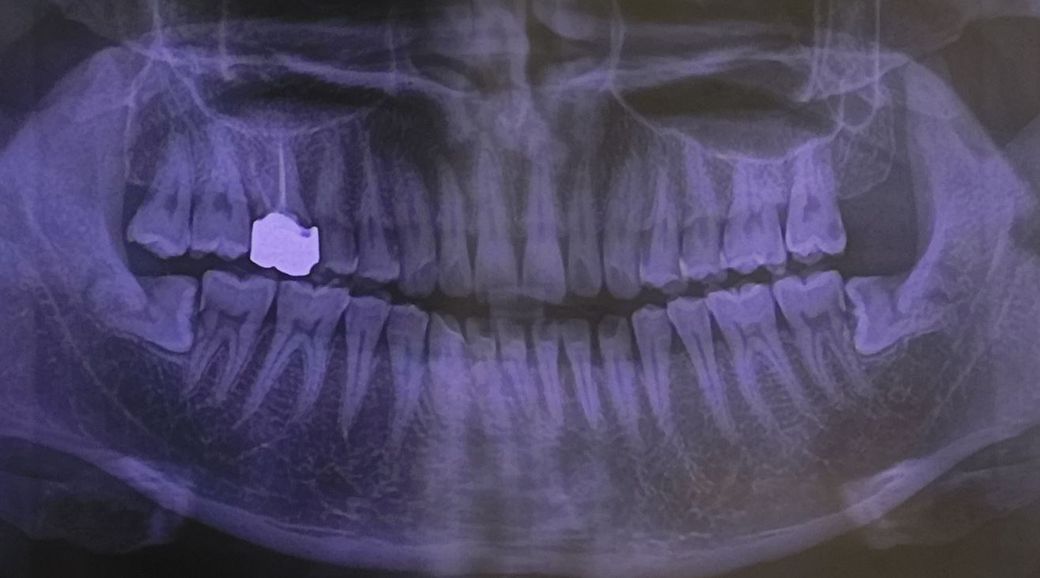

사진상으로 위 오른쪽끝 어금니에서 네번째 이가 지금 밑사진 첫번째 검은 부분인데 이게 범랑질 안에서 어렸을때부터 충치가 자란거라하더라구요 상태가 심각한가요?

두번째사진이 사진상 왼쪽 끝 어금니 상태인데 제가봐도 좀 심각해보이는데 상태많이안좋은가요?

• 안녕하세요 치과의사 김철진입니다. 위에 사진상으로 보면 작은어금니의 충치는 많이 진행된거 같습니다. 맨 마지막사진은 일단은 스켈링으로 제거를 해보고 안되면 간단히 충치치료를 해야될것같습니다.

• 사진으로는 정확한 판단이 어려워 보이지만 작은 어금니의 경우에는 내부에 충치가 있는것으로 판단됩니다.

사랑니 앞에 있던 치아도 방사선상에 어두운면이 보이는것으로 보아 충치가 의심되지만 큰 충치는 아닐수 있습니다.

정확한 확인을 위해서는 치과에서 진료를 받아보는것이 좋습니다.